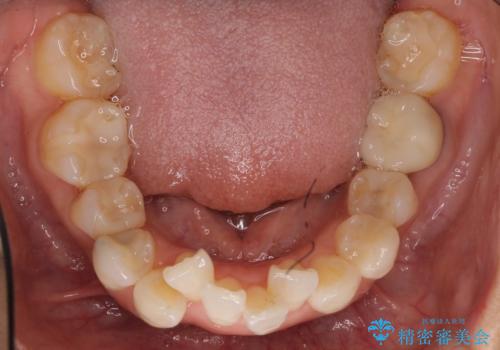

- 上下の歯のがたつきを主訴に来院されました。

上下の前歯の叢生とかみ合わせが深い過蓋咬合という状態でした。

上下左右の歯を1本ずつ抜歯して、ワイヤーにて矯正を行いました。